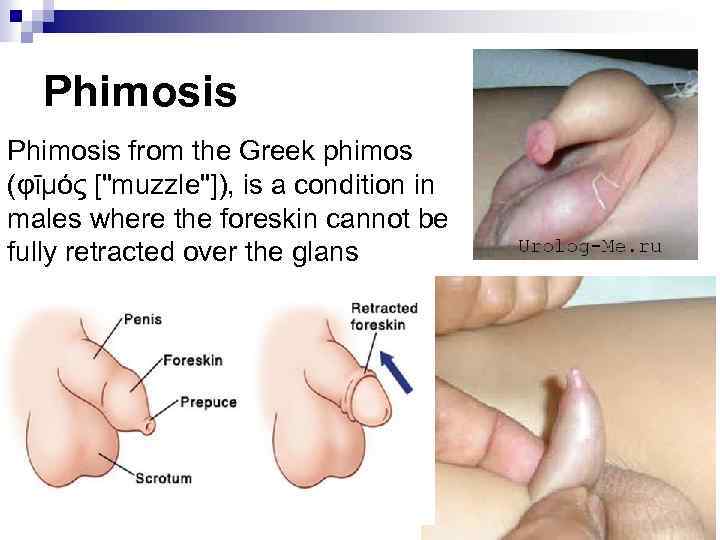

Phimosis from the Greek phimos (φῑμός ["muzzle"]), is a condition in males where the foreskin cannot be fully retracted over the glans penis.

Phimosis from the Greek phimos (φῑμός ["muzzle"]), is a condition in males where the foreskin cannot be fully retracted over the glans penis.